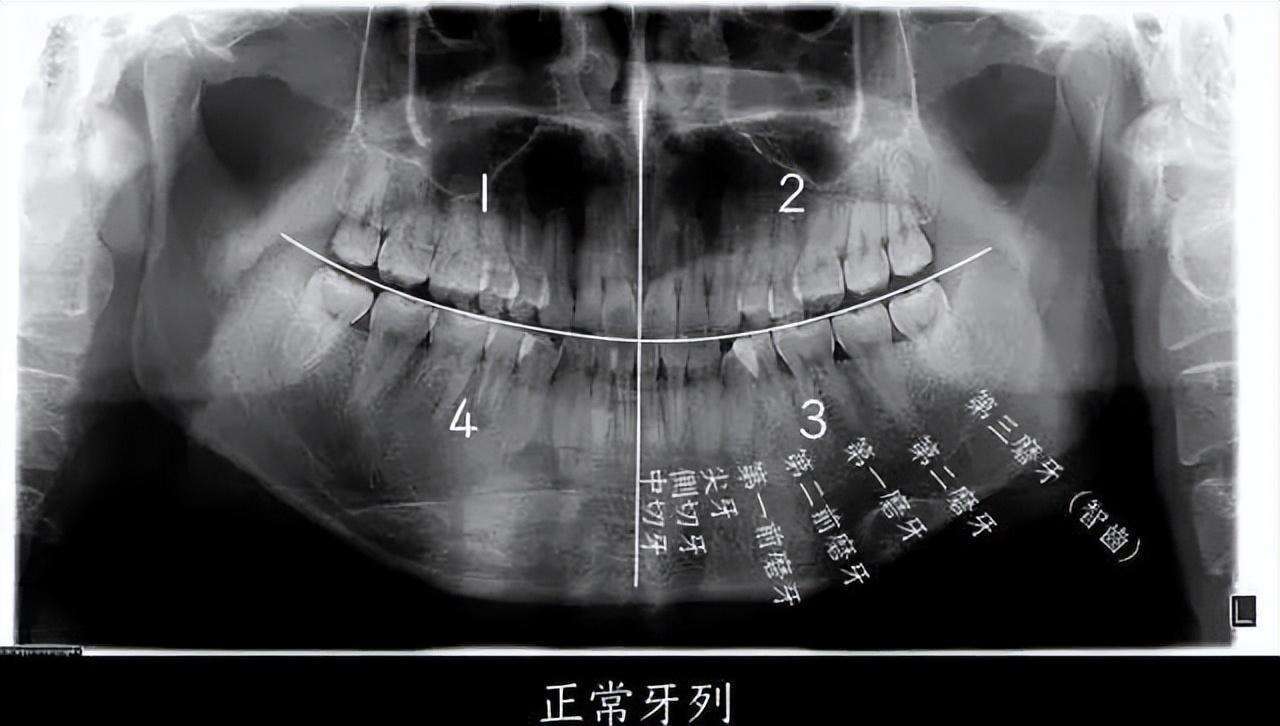

▲ 智齿即第三磨牙,位于口腔最远最深位置

图源:浙江大学医学院附属第二医院何剑亮医生

如果把一个正常成年人的口腔分为左上、左下、右上、右下四个区域的话,每个区域会有 8 个牙齿,长在最后的第8颗牙齿,就是我们口中的“智齿”,即第三磨牙。